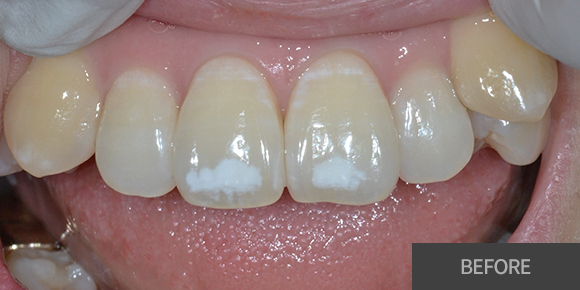

심미레진

전체미백

실활치미백